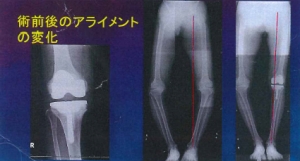

現在、変形性膝関節症の手術で最も多く行われているのが、人工膝関節置換術です。関節全体を入れ換える手術ではなく、痛みの原因であるすり減った軟骨と傷んだ骨の表面部分を切除して、金属やプラスチックでできた人工の関節に置き換える手術です。痛みの大きな改善と、早期の回復が期待できる治療法です。

膝関節の損傷が比較的軽度の患者さんの場合、膝の片側だけを置き換える人工膝関節部分置換術が適用できる場合があります。膝全体を置換する全置換術と比べて小さな人工関節のため、骨を削る量や手術の傷も小さく、より早期の回復が望めます。